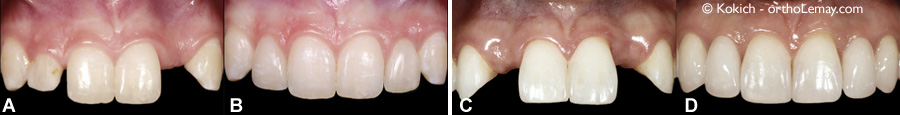

(A) Incisive latérale droite courte et étroite, absence congénitale (anodontie) de l’incisive latérale gauche. (B) Le contour gingival des incisives centrale et latérale droites furent modifiés pour être plus harmonieux avec les mêmes dents du côté opposé et l’incisive latérale droite fut rebâtie en matériau composite. Un implant dentaire remplace l’incisive latérale gauche. (C) Anodontie des 2 latérales chez une jeune femme de 19 ans. (D) Des ponts fixes en porte-à-faux (“cantilevered bridges”) ancrés sur les canines remplacent les incisives latérales.